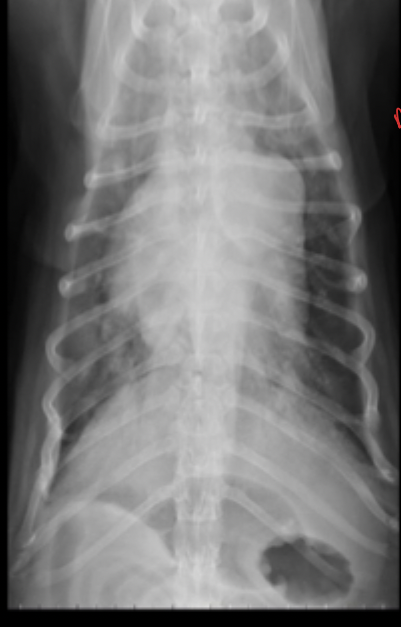

What can be seen in these cat radiographs?

Nothing, these radiographs are normal